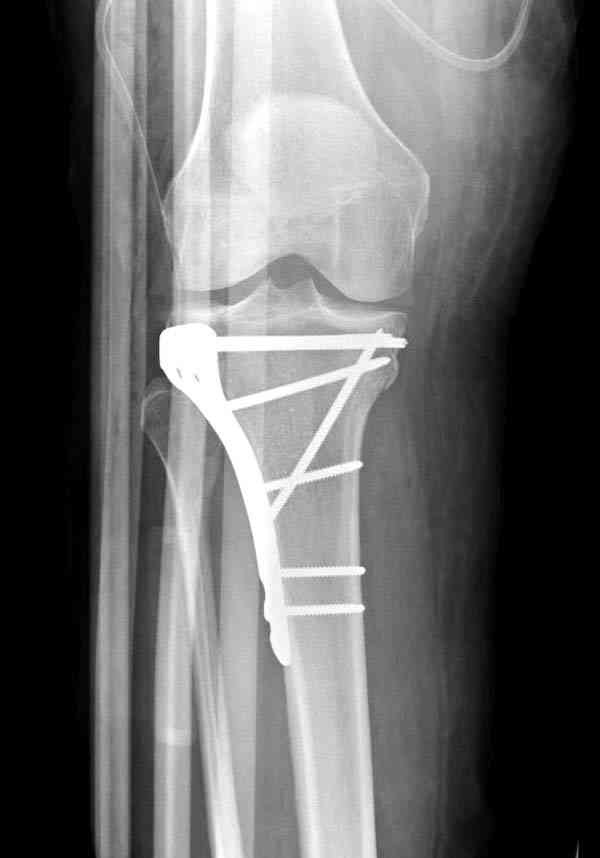

Из медиального окна можно приподнять латеральную

импрессию. Фиксация тремя параллельными шурупами в

эпифизарной части над импрессией. Создается крыша,

которая предупредит коллапс. На образовавшуюся полость - костная пластика из аутокости или синтетический заменитель. Мы применяем Osteoset в 4-5 мм диаметре таблеточки или иньекционную форму Prodens.

После заполнения образовавшейся полости в метафизе

кортикальное окно можно прикрыть.

Это техника применяется, когда имеется

центральная импрессия, а при ипрессии с краевым переломом - после приподнимания импрессии опорная (Butress) пластина, как на снимке.